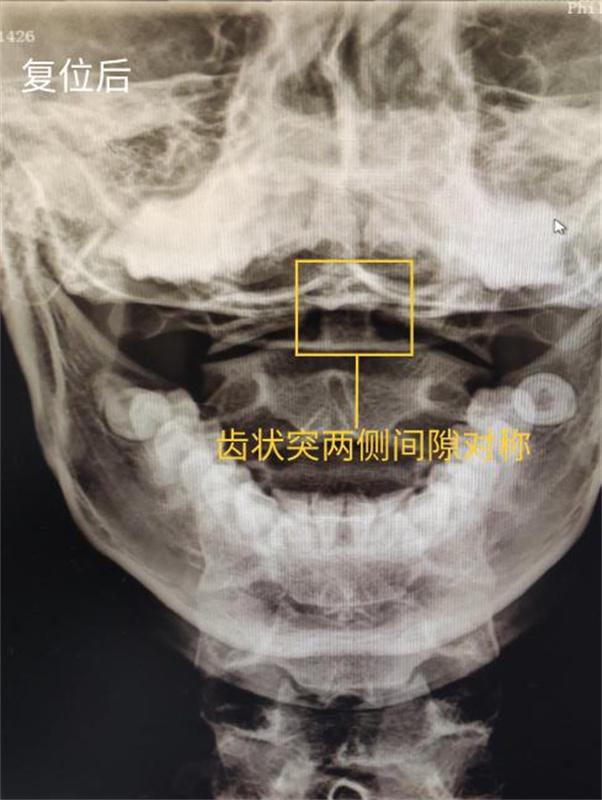

△ 复位后

一周后,医生电话随访,小陈表示头痛症状消失,颈部稍有不适。医生告诉他,这是因为寰枢关节半脱位时间较久,颈部双侧肌肉力量欠均衡,必要时可至门诊随诊。